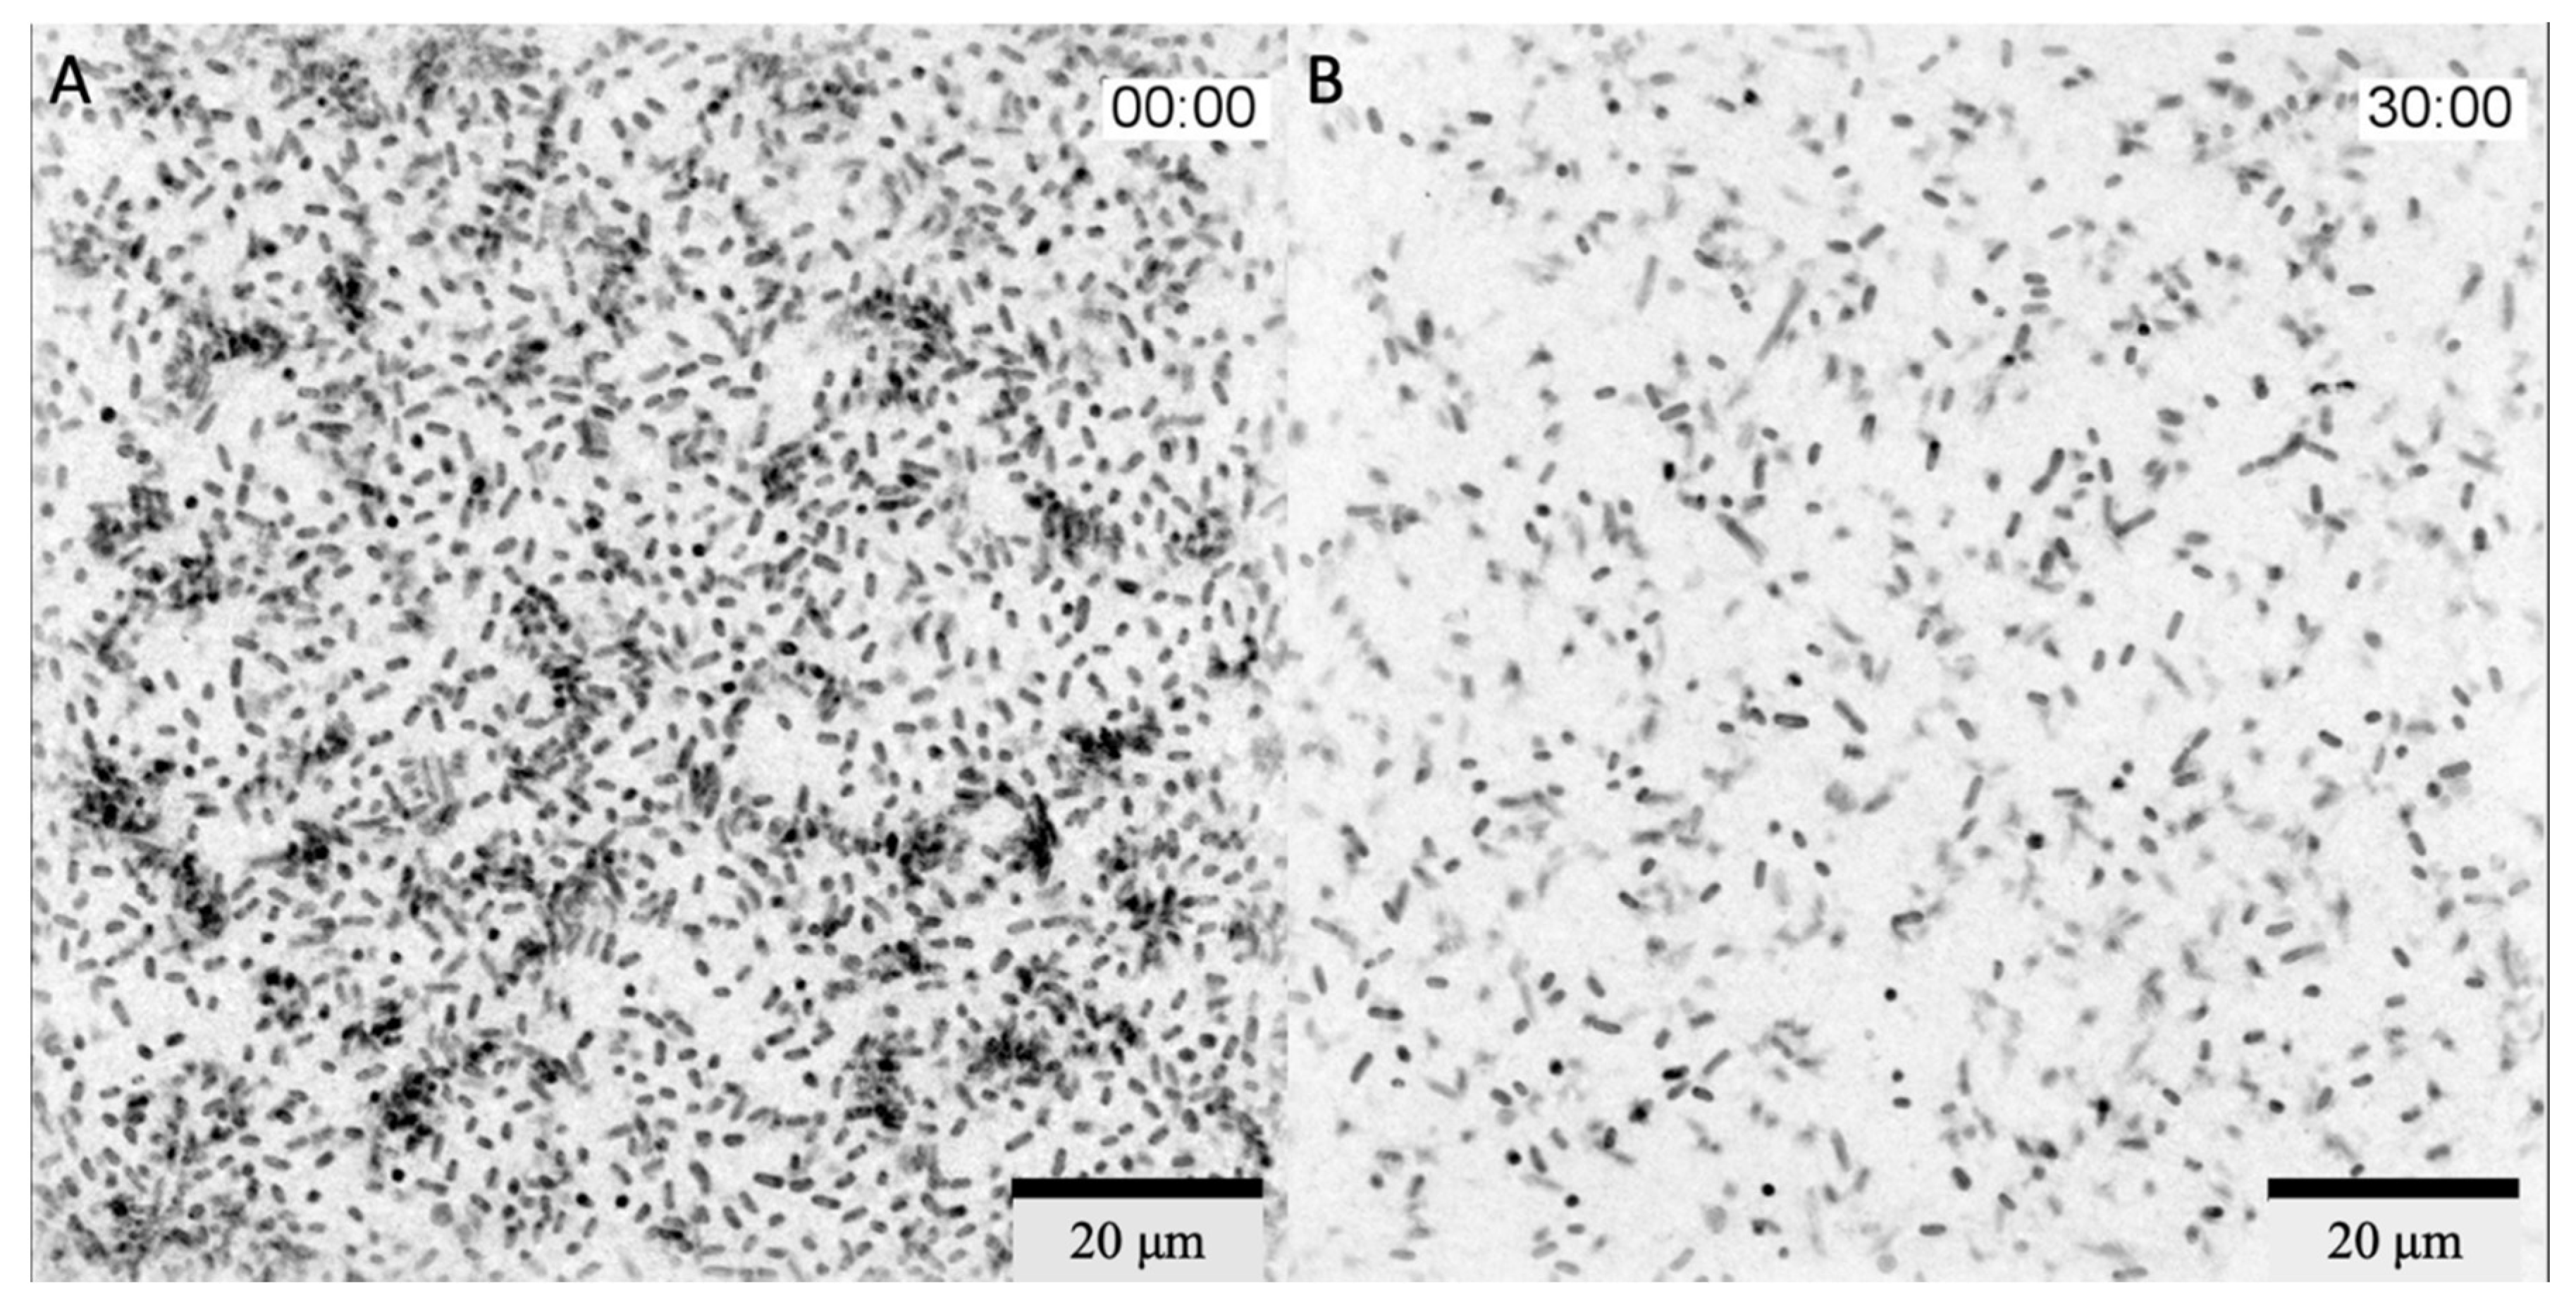

In Vitro Real-Time Phage Lysis Assay